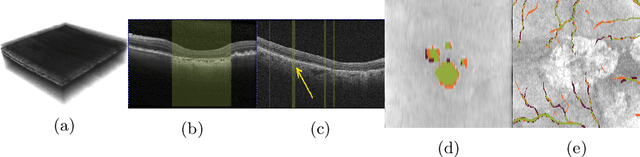

Abstract:Deep learning has become a valuable tool for the automation of certain medical image segmentation tasks, significantly relieving the workload of medical specialists. Some of these tasks require segmentation to be performed on a subset of the input dimensions, the most common case being 3D-to-2D. However, the performance of existing methods is strongly conditioned by the amount of labeled data available, as there is currently no data efficient method, e.g. transfer learning, that has been validated on these tasks. In this work, we propose a novel convolutional neural network (CNN) and self-supervised learning (SSL) method for label-efficient 3D-to-2D segmentation. The CNN is composed of a 3D encoder and a 2D decoder connected by novel 3D-to-2D blocks. The SSL method consists of reconstructing image pairs of modalities with different dimensionality. The approach has been validated in two tasks with clinical relevance: the en-face segmentation of geographic atrophy and reticular pseudodrusen in optical coherence tomography. Results on different datasets demonstrate that the proposed CNN significantly improves the state of the art in scenarios with limited labeled data by up to 8% in Dice score. Moreover, the proposed SSL method allows further improvement of this performance by up to 23%, and we show that the SSL is beneficial regardless of the network architecture.

Abstract:In medical imaging, there are clinically relevant segmentation tasks where the output mask is a projection to a subset of input image dimensions. In this work, we propose a novel convolutional neural network architecture that can effectively learn to produce a lower-dimensional segmentation mask than the input image. The network restores encoded representation only in a subset of input spatial dimensions and keeps the representation unchanged in the others. The newly proposed projective skip-connections allow linking the encoder and decoder in a UNet-like structure. We evaluated the proposed method on two clinically relevant tasks in retinal Optical Coherence Tomography (OCT): geographic atrophy and retinal blood vessel segmentation. The proposed method outperformed the current state-of-the-art approaches on all the OCT datasets used, consisting of 3D volumes and corresponding 2D en-face masks. The proposed architecture fills the methodological gap between image classification and ND image segmentation.